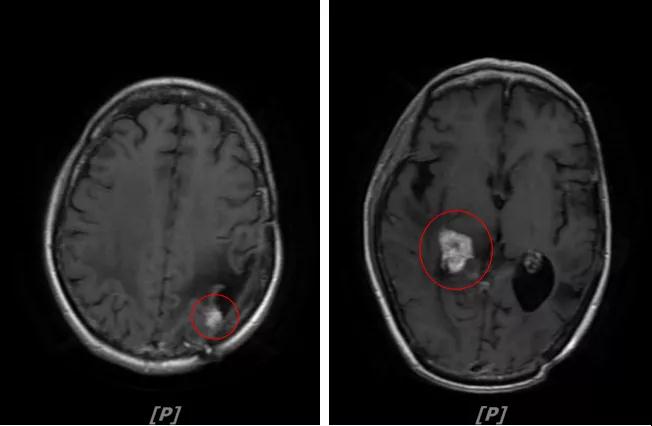

4.病情第3次进展:2018年10月患者头痛症状又加重

头颅增强MR:左侧顶颞叶见片状T1WI低信号、T2WI高信号影,病灶大部信号接近脑脊液;增强后可见左侧额叶、顶叶、两侧海马及右侧小脑半球呈多发斑点状、结节样明显强化,大者大小约14x11mm,较2016-12-11增强老片病灶增大、增多;两侧半卵圆区、侧脑室旁见较对称片状T1WI低信号、T2WI高信号影,增强后未见明显强化( 较2017-8-9MR老片稍明显) ;余脑室、脑池、脑沟大小形态可,中线结构居中无移位。左侧上颌窦粘膜轻度增厚

左顶颞叶转移瘤治疗后改变;脑内多发强化灶,考虑转移,较前增大增多

两侧脑室旁云絮状异常信号:考虑放疗后改变

患者二线治疗的PFS为22个月,2018年11月患者给予后续解救治疗为吡咯替尼(400mg/d)联合阿那曲唑;患者头痛症状好转,病灶继续缩小,继续定期复查。